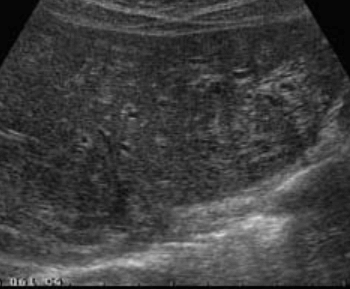

US finding

- 조기에 말초지 담관확장소견이 보인다.

- 간내담관암은 주변 간조직과 흐릿한 경계를 보인다.

- 종괴의 크기가 커질수록 고에코로 보인다.